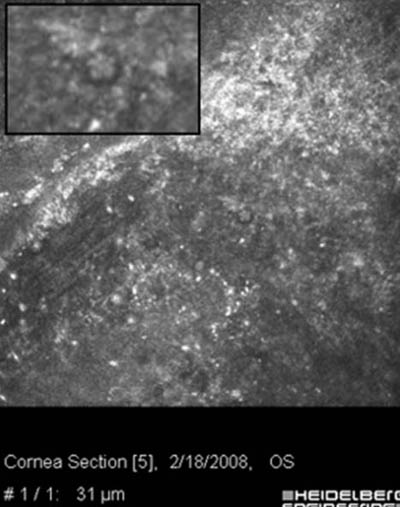

Microscopía Confocal

- Microscopia Confocal : 94 a 100% de especificidad y 80 a 84% de sensibilidad